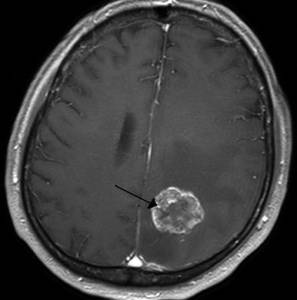

Злокачественная опухоль

Злокачественная опухоль характеризуется появлением патологического новообразования, опасного для человеческой жизни, состоящего из злокачественных раковых клеток, обладающих возможностью быстрого роста и метастазирования.

Тип боли

Интенсивность и характер болевого синдрома зависит от локализации опухоли, тяжести процесса, индивидуальных особенностей организма.

Другие проявления

На начальных стадиях опухоль может никак себя не проявлять вплоть до интенсивного роста новообразования. Тогда самочувствие пациента начинает резко ухудшаться, могут возникать: тошнота, утомляемость, рвота, нарушение слуха и зрения, трудности распознавания речи, расстройства общей и мелкой моторики и т.д.

Клиническая картина при раке очень обширна и многогранная.

Методы диагностики и терапии

Диагностика проводится комплексно и включает: КТ, МРТ, рентгенологическое исследование, лабораторные анализы, гистологию и цитологию. Лечение проводится хирургическое. Пациенту может быть назначен курс химиотерапии или лучевой терапии, а затем длительное медикаментозное поддерживающее лечение.

- Опухоль головного мозга. Часто при возникновении злокачественных образований пациенты жалуются на боль в голове и слабость. Еще одним симптомом является тошнота, которая возникает, как правило, по утрам.